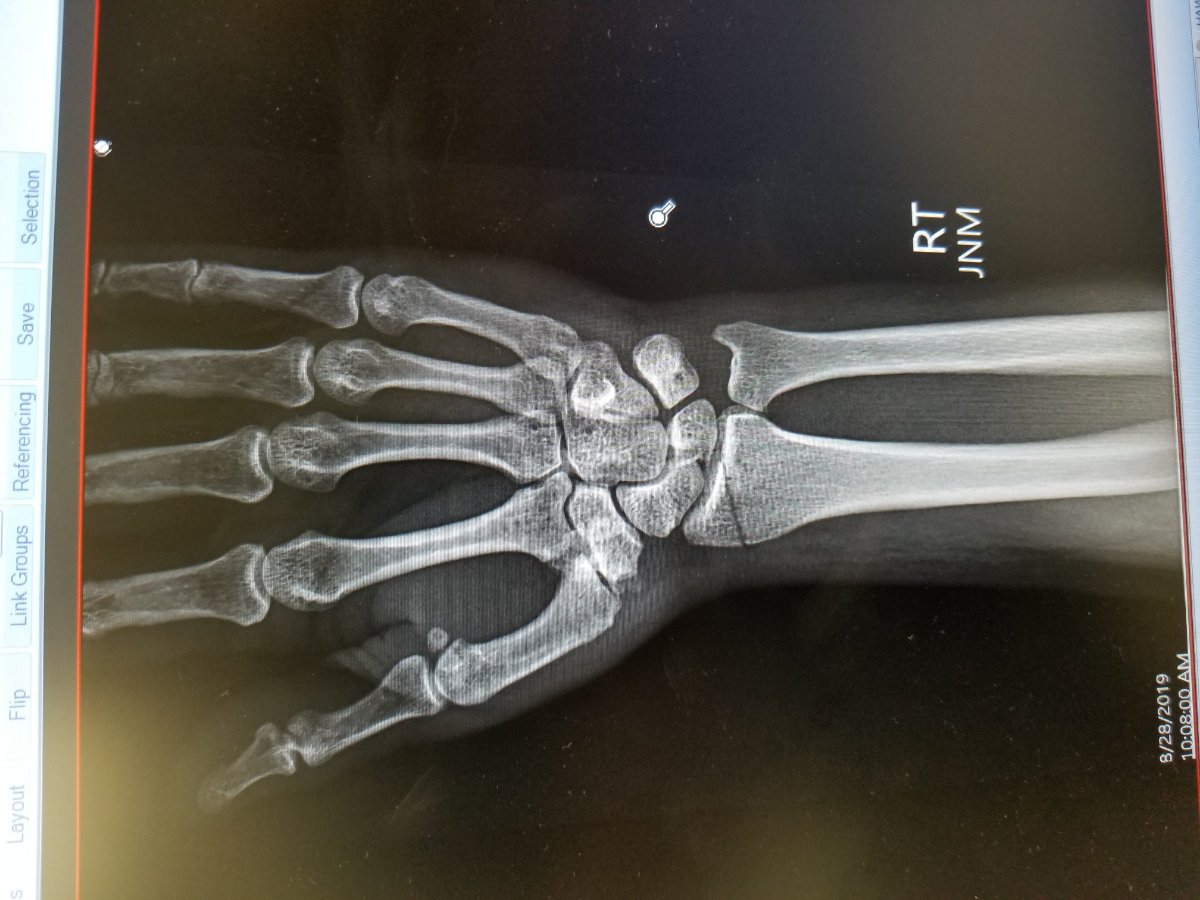

My T broke my wrist DAMN

Right arm near wrist.